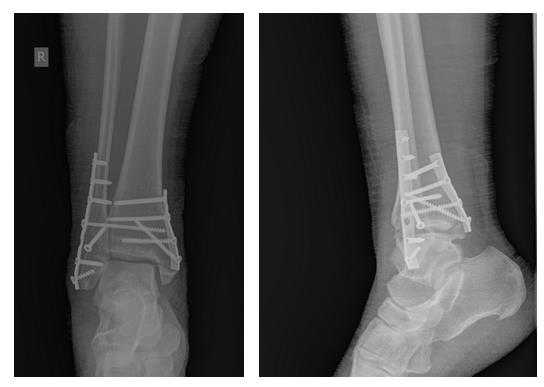

Клинический случай 1. Перелом обеих лодыжек с подвывихом стопы кнаружи.

Пациентка Т. 80 лет. Травма за 3 недели до обращения, получила перелом обеих лодыжек правой голени со смещением, подвывихом стопы кнаружи. Обратилась в РТП, выполнена рентгенография, наложена гипсовая повязка. В связи с сохраняющимся выраженным отёком и болевым синдромом обратилась в клинику К+31.

На рентгенограммах в гипсе определяется значительный подвывих таранной кости кнаружи, консолидирующийся перелом нижней трети малоберцовой кости.

В день обращения пациентка послоностью обследована, проведено оперативное лечение, открытая репозиция, остеосинтез перелома нижней трети малоберцовой кости пластиной, внутренней лодыжки винтом, внутренняя лодыжка дополнительно фиксирована анкерным фиксатором.

На контрольных рентгенограммах после операции положение отломков, металлофиксаторов правильное, подвывих таранной кости устранён.

Пациентка выписана на 2 сутки после операции на амбулаторное долечивание.